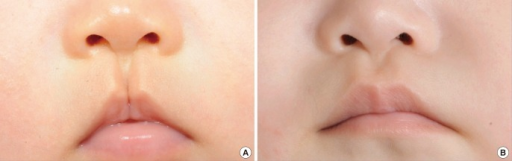

Cleft Lip

The five facial prominences grow and usually unite to create the face during the early stages of pregnancy.

The five facial prominences include:

- One superior

- One left

- One right

- Two inferiors

A cleft lip is a full thickness lip deformity brought on by the failure of the facial prominences to fuse together.

Cleft palate frequently coexists with cleft lip.

Cleft Palate

A complete thickness deformity in the palate known as cleft palate results from the inability of the facial prominences to fuse.

Cleft lip frequently coexists with cleft palate.

A single cleft palate is less frequent.